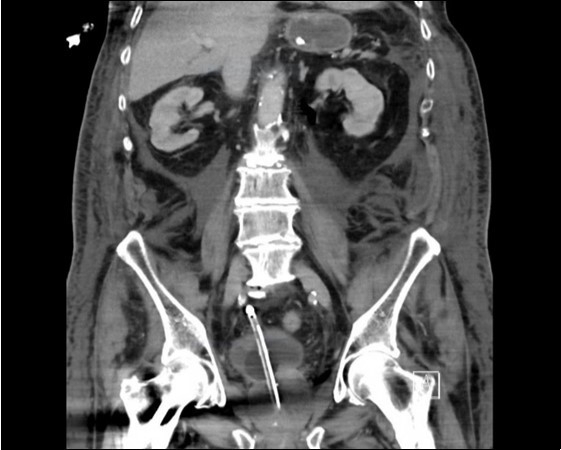

An urgent CT abdomen revealed a bladder perforation with the tip of the irrigating catheter situated in the abdominal cavity (Figure 1, Figure 2, Figure 3a,Figure 3b). This was most likely due to over-insertion of the 3-way catheter due to the extra force required because of the benign prostatic hypertrophy. He had therefore been receiving normal saline as ‘peritoneal dialysis’ with normal saline since insertion of the catheter. The catheter was withdrawn, and the patient made a full recovery.

Figure 3a.horizontal plane CT image 2

horizontal plane CT image 2